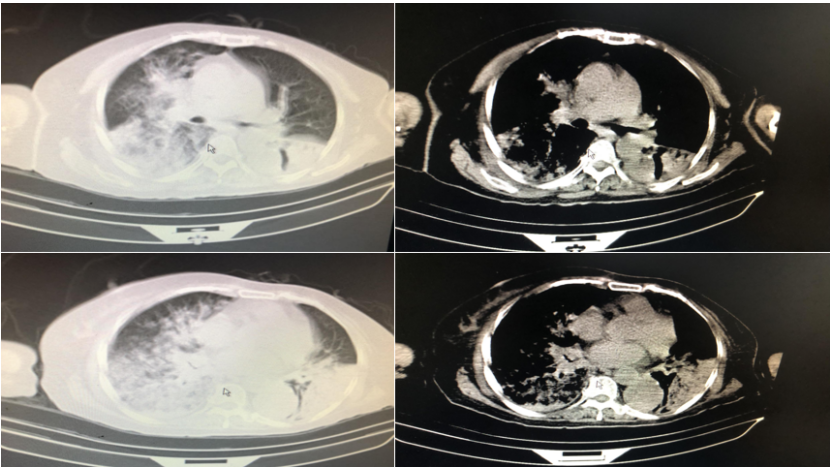

辅助检查:①血常规:WBC 15.73×109/L,NEU% 90%,Hb 90 g/L。②生化:谷丙转氨酶22 U/L,白蛋白22.5 g/L,尿素氮7.31 mmol/L,肌酐68.1 μmol/L,葡萄糖7.94 mmol/L,血钾3.35 mmol/L,钠135.4 mmol/L。③炎症指标:PCT 2.4 ng/ml,ESR 116 mm/h,CRP 137 mg/L。④影像学:11月29日胸部CT示双肺大面积感染(图1)⑤11月30日床旁电子支气管镜检查提示气管及左右主支气管腔内大量绿脓痰(图2)。⑥11月30日血气分析:pH 7.54,PaCO2 33.4 mmHg,PaO2 54 mmHg,HCO3- 28.6 mmol/L。

图片

图1  患者胸部CT(2020-11-29)

治疗效果:患者炎症指标(WBC、CRP、PCT、ESR)逐渐下降(表3),体温下降并恢复正常。血气分析(不吸氧)示pH 7.42,PaCO2 42.4 mmHg,PaO2 91 mmHg。12月13日胸部CT示病变吸收(图4)

图4 患者胸部CT(2020-12-13)